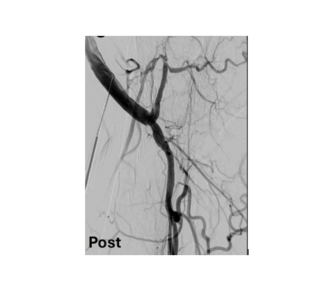

The authors report a case of recurrent superficial femoral artery occlusion that necessitated the use of endovascular intervention with image-guided stent placement.